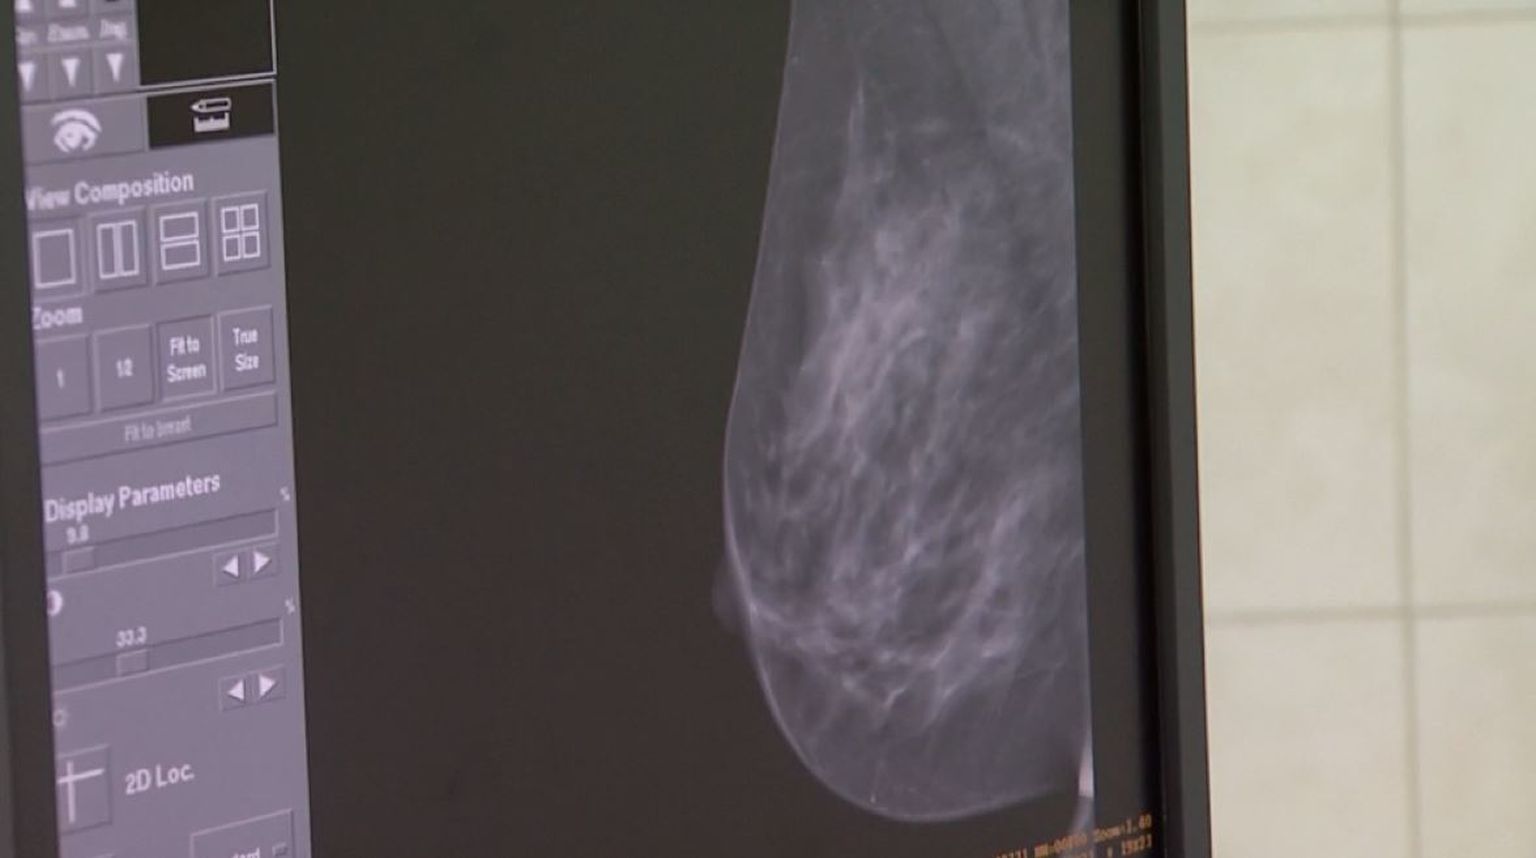

Pilot-projekt: Uz PAPA test, ženama bi na raspolaganju uskoro mogao biti i primarni test na HPV